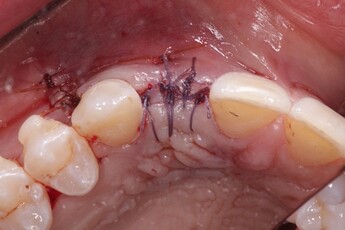

Pic 8

osseoseal-8

An implant was placed in site #7 with an existing buccal bone defect (Pictures 1 & 2). Prior to placing the bone graft over the implant, the membrane is measured and trimmed and tucked under the palatal flap trying to avoid wetting the entire membrane (Picture 3). The particulate bone graft (DALI Classic Cortical Cancellous Mix) is placed over the implant surface to restore the defect (Picture 4). The membrane is folded over the crest and onto and slightly beyond the particulate bone graft while slowly dropping saline onto the membrane (Picture 5). This enables the membrane to contour and drape over the graft and “seal” the graft off from the surrounding soft tissue (Picture 6 and 7). Sutures are then used to achieve primary closure over the GBR site (Picture 8).